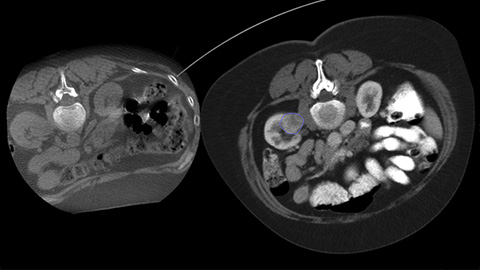

By opening the arc to the left of the patient, CBCT allows off center positioning of the patient table and therefore better centering of the FOV. It significantly increases image coverage to help visualize tumors on the periphery of the organ [2].

Percutaneous ablation (radiofrequency, microwave, and cryoablation) is a well-established minimally invasive treatment of kidney, liver, lung and bone tumors. The key is gaining a clear understanding of the tumor size, needle ablation area, and optimal path to the target. Onco suite provides tools to help you:

Dual View allows the overlay of a pre-procedure 3D image (CT/MR/PET-CT) on an intra-procedure 3D CBCT to better visualization the lesions and access critical input for needle planning [8].